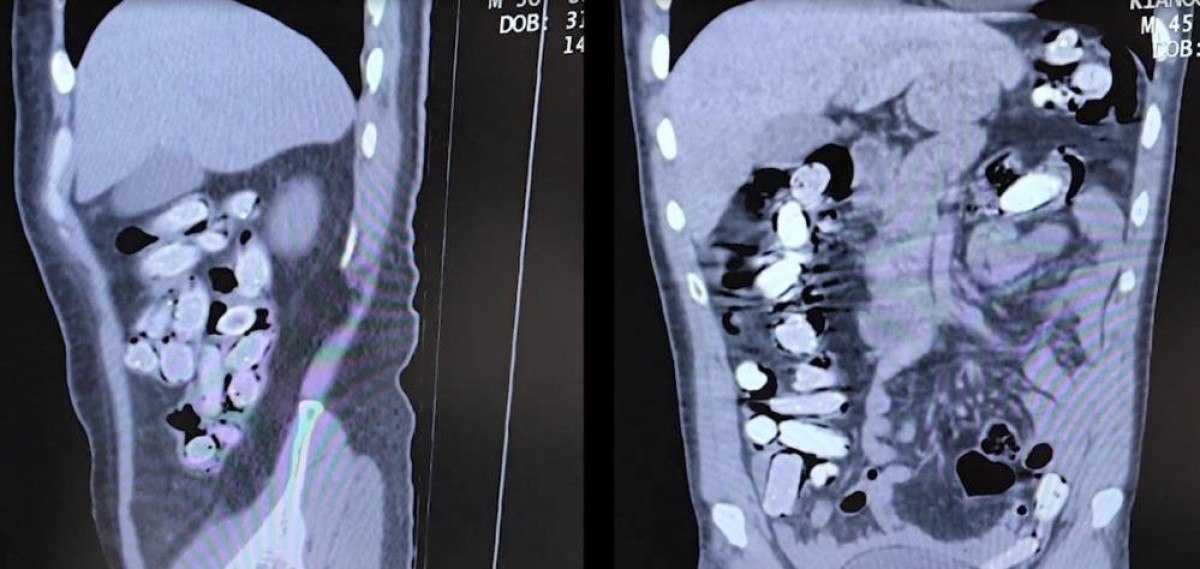

Tatvan Devlet Hastanesine sevk edilen şüphelilerin röntgen ve tomografi görüntülerinde mide ile bağırsaklarında çok sayıda yabancı cisim bulunduğu tespit edildi.

Yapılan tıbbi müdahale ile şüphelilerin paketleyerek yuttuğu toplam 96 adet daralı ağırlığı 1 kilogram 340 gram Afyon sakızına el konuldu.